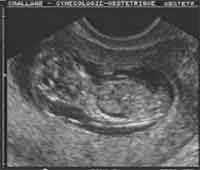

Épanchement thoracique